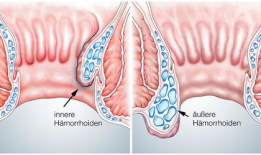

女性混合痔疮手术视频,女性混合痔疮手术过程解析与康复指导

你有没有想过,当女性朋友们面对混合痔疮这个尴尬的问题时,她们会选择怎样的方式来了解和治疗呢?今天,就让我带你一探究竟,揭秘女性混...

2025-07-23 146 -